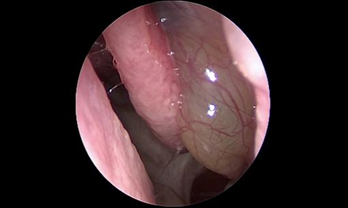

- Phát hiện sớm các trường hợp polyp mũi xoang, ung thư vòm họng qua nội soi.

- Phẫu thuật nội soi mở dẫn lưu các xoang sàng, hàm, trán, bướm điều trị viêm xoang mạn tính

- Phẫu thuật nội soi cắt polyp mũi

- Phẫu thuật nội soi mũi xoang điều trị các viêm xoang đặc biệt: viêm xoang do nấm, viêm xoang do răng

- Phẫu thuật nội soi mũi xoang điều trị các khối u: u nhú mũi xoang, u nhầy.

- Phẫu thuật nội soi mũi xoang với hệ thống định vị trong lúc mổ (Navigation) cho phép bác sĩ tiếp cận trực tiếp đến các vùng mũi xoang bị viêm, gia tăng khả năng quan sát các mốc giải phẫu trong hốc mũi để đánh giá một cách chính xác các bệnh lý sâu trong hốc mũi.

- Trên cơ sở đó, bác sĩ có thể dễ dàng thao tác loại bỏ sạch các tác nhân gây viêm và mủ mà vẫn bảo tồn tối đa niêm mạc lành và hạn chế nạo bỏ niêm mạc triệt để, tối ưu lưu thông không khí trong hệ thống xoang.

- Hỗ trợ đắc lực cho các ca phẫu thuật xoang tại bệnh viện SIS Cần Thơ là hệ thống nội soi Karl Storz cùng máy chụp cắt lớp thế hệ mới nhất CT photon, cho phép phát hiện những tổn thương nhỏ tại hốc mũi xoang. Bên cạnh đó, máy khoan cắt hút mô liên tục đa chức năng Nouvag của Thụy Sĩ giúp tăng độ chính xác, giảm tổn thương niêm mạc, rút ngắn thời gian phẫu thuật.